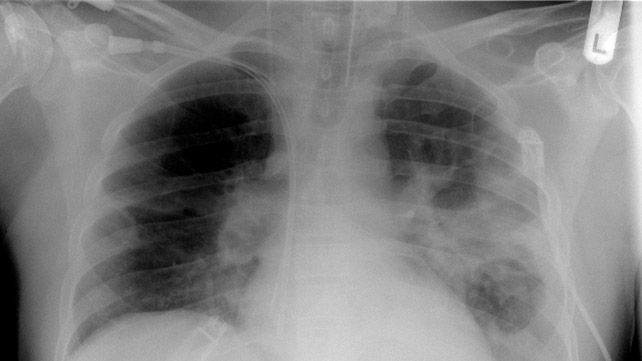

肺炎

肺炎是导致肺部感染的原因:

- 发热

- 胸痛

- 呼吸困难

- 咳嗽产生粘液

那些免疫系统被另一种疾病削弱的人可能会患上更为危险的肺炎。